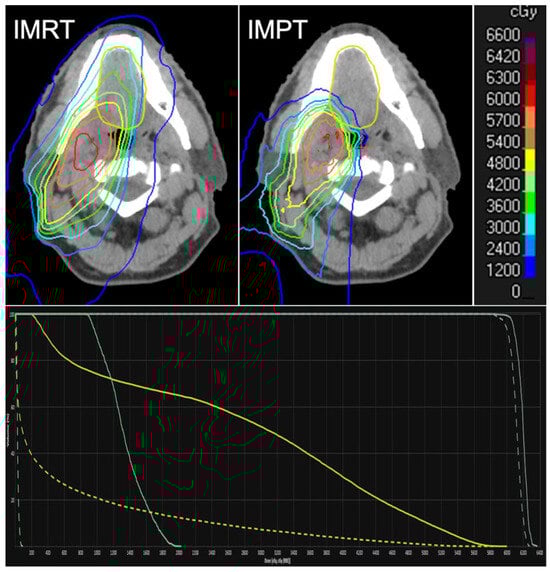

4. Proton Therapy

- Blanchard, P.; Garden, A.S.; Gunn, G.B.; Rosenthal, D.I.; Morrison, W.H.; Hernandez, M.; Crutison, J.; Lee, J.J.; Ye, R.; Fuller, C.D.; et al. Intensity-modulated proton beam therapy (IMPT) versus intensity-modulated photon therapy (IMRT) for patients with oropharynx cancer—A case matched analysis. Radiother. Oncol. 2016, 120, 48–55. [Google Scholar] [CrossRef]

- Manzar, G.S.; Lester, S.C.; Routman, D.M.; Harmsen, W.S.; Petersen, M.M.; Sloan, J.A.; Mundy, D.W.; Hunzeker, A.E.; Amundson, A.C.; Anderson, J.L.; et al. Comparative analysis of acute toxicities and patient reported outcomes between intensity-modulated proton therapy (IMPT) and volumetric modulated arc therapy (VMAT) for the treatment of oropharyngeal cancer. Radiother. Oncol. 2020, 147, 64–74. [Google Scholar] [CrossRef]

- Youssef, I.; Yoon, J.; Mohamed, N.; Zakeri, K.; Press, R.H.; Chen, L.; Gelblum, D.Y.; McBride, S.M.; Tsai, C.J.; Riaz, N.; et al. Toxicity Profiles and Survival Outcomes Among Patients With Nonmetastatic Oropharyngeal Carcinoma Treated With Intensity-Modulated Proton Therapy vs Intensity-Modulated Radiation Therapy. JAMA Netw. Open 2022, 5, e2241538. [Google Scholar] [CrossRef]

- Frank, S.J.; Busse, P.; Rosenthal, D.I.; Hernandez, M.; Swanson, D.M.; Garden, A.S.; Sturgis, E.M.; Ferrarotto, R.; Gunn, G.B.; Patel, S.H.; et al. Phase III randomized trial of intensity-modulated proton therapy (IMPT) versus intensity-modulated photon therapy (IMRT) for the treatment of head and neck oropharyngeal carcinoma (OPC). J.Clin. Oncol. 2024, 42, 6006. [Google Scholar] [CrossRef]